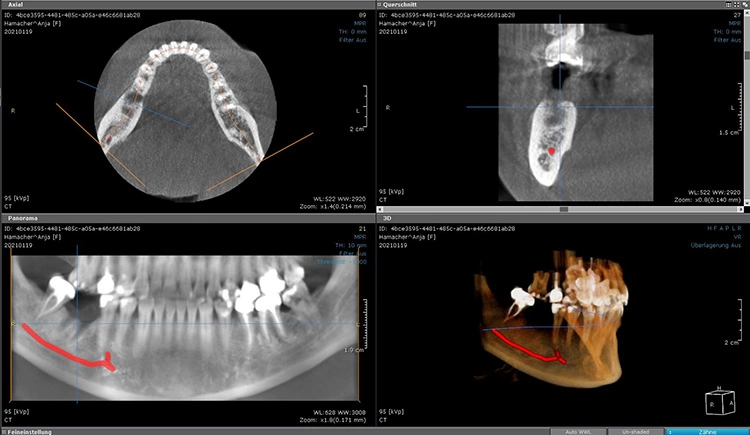

Drei Monate nach der Extraktion des nicht erhaltungswürdigen Zahnes 46 wurde im Januar 2021 eine DVT angefertigt (Abb. 2) und es wurden Ober- und Unterkiefer abgeformt. Für die Planung der Bohrschablonen (Fremdlabor) erfolgte die Digitalisierung der Modelle mit einem Laborscanner im Eigenlabor, anschließend wurden die Daten an den Planungspartner zur Herstellung der Bohrschablonen übermittelt. Dort erfolgte die digitale Vorplanung der Implantatposition und der prothetischen Versorgung mit der Planungssoftware coDiagnostiX (dental wings) (Abb. 3 und 4).